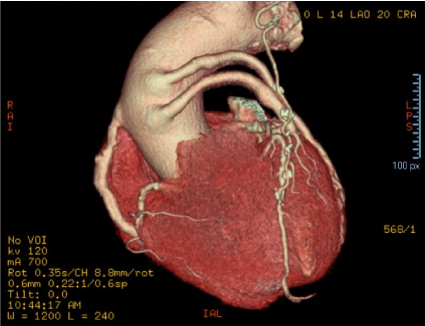

The patient EDAV, with 68-years old, due to coronary artery disease received saphenous grafts. After the last angiotomography of the coronary arteries by computed tomography performed in 2019, May-21, aortic root ectasia was measured, measuring 39 × 40 × 42 mm and GASV, as well as mural atheromatosis in the thoracic aorta, as shown in Figures 1, Figure 2 and Figure 3.

Figure 2: Angiotomography examination of the coronary arteries, showing the saphenous vein aneurysm grafted by the angle of observation 2. View Figure 2